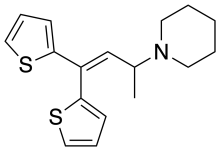

Thiambutenes

Structures